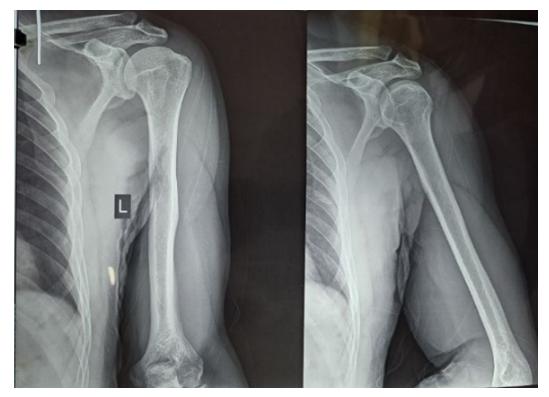

Clinical Case. Patient S.Yu., born 1974. Case No. 738/2024.The patient presents with complaints of pain and deformity in the left shoulder area. Medical history: On 14.01.2024, during a football training session, a "popping" sound was heard. After 2 days, pain, swelling, and deformity appeared. The patient underwent standard examination procedures and was diagnosed with: Rupture of the long head tendon of the left biceps brachii muscle. On 19.01.2024, the patient underwent surgical procedure No. 171 "Fixation of the long head tendon of the left biceps muscle."Ultrasound examination provided the following conclusion: Echo signs of rupture of the long head tendon of the biceps brachii muscle with hematoma formation, and tendinopathy of the rotator cuff tendons of the left shoulder joint are detected.Radiological examination revealed signs of primary osteoarthritis in the acromioclavicular joint. | Figure 2. Patient S.Yu. X-ray analysis |